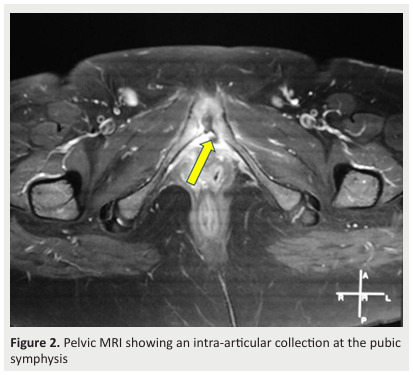

Introduction-Aim: Postpartum septic osteoarthritis is a rare but serious condition often misdiagnosed due to overlap with common postpartum symptoms like pelvic pain and joint stiffness. This case series aims to describe the clinical, bacteriological, and radiological characteristics of postpartum septic osteoarthritis, as well as the treatment approaches and patient outcomes. Methods: A retrospective case series was conducted at Farhat Hached University Hospital, from 2006 to 2022, involving patients with confirmed postpartum septic osteoarthritis. Clinical data, laboratory findings, imaging results, treatments, and outcomes were analyzed Results: The mean age of the seven patients was 31.4 years. All patients presented with joint pain, with fever and functional impairment where each was observed in 85.7% of cases. The average diagnostic delay was 17 days. MRI findings revealed bone marrow edema in all patients, Abscesses in 28.5% of cases, periarticular soft tissue edema, and intra-articular effusions in 71.4% of cases. The pubic symphysis was the most commonly affected site (57.1%), followed by the sacroiliac joints (28.6%). Only one pathogen, Streptococcus pyogenes, was isolated. Nearly all patients received dual antibiotic therapy for an average duration of 4 to 6 weeks. Satisfactory clinical progress without sequelae was noted and maintained after an average follow-up of 5 to 6 months. .Conclusion: Our results revealed that postpartum septic osteoarthritis requires prompt diagnosis and early treatment to prevent severe complications. MRI plays a critical role in early detection, while timely antibiotic therapy leads to favorable long-term outcomes.